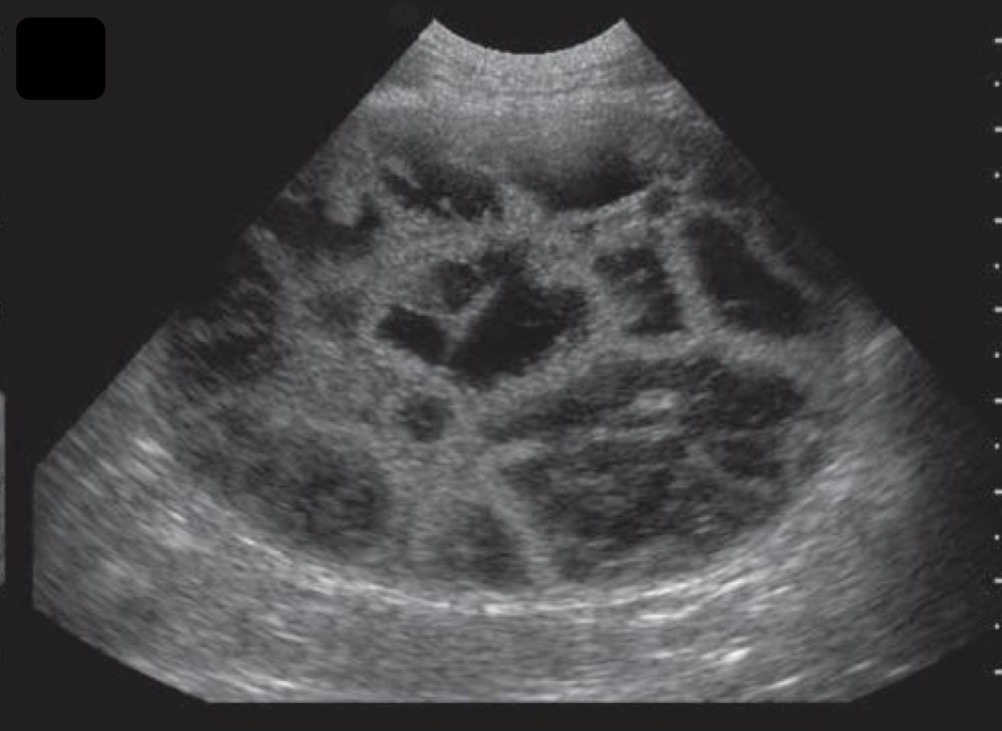

Multiple hypo echoic nodules

What could cause the spleen to have a Swiss cheese appearance on an ultrasound?

Spleen

What organ is this a ultrasound of?